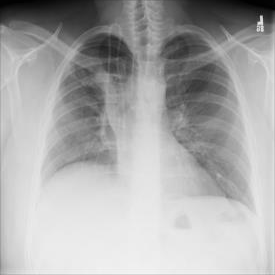

The COVID-19 disease was first discovered in Wuhan, China, and spread quickly worldwide. After the COVID-19 pandemic, many researchers have begun to identify a way to diagnose the COVID-19 using chest X-ray images. The early diagnosis of this disease can significantly impact the treatment process. In this article, we propose a new technique that is faster and more accurate than the other methods reported in the literature. The proposed method uses a combination of DenseNet169 and MobileNet Deep Neural Networks to extract the features of the patient's X-ray images. Using the univariate feature selection algorithm, we refined the features for the most important ones. Then we applied the selected features as input to the LightGBM (Light Gradient Boosting Machine) algorithm for classification. To assess the effectiveness of the proposed method, the ChestX-ray8 dataset, which includes 1125 X-ray images of the patient's chest, was used. The proposed method achieved 98.54% and 91.11% accuracies in the two-class (COVID-19, Healthy) and multi-class (COVID-19, Healthy, Pneumonia) classification problems, respectively. It is worth mentioning that we have used Gradient-weighted Class Activation Mapping (Grad-CAM) for further analysis.

翻译:COVID-19 疾病在中国武汉首次发现,并迅速蔓延到全世界。在COVID-19 流行病后,许多研究人员开始寻找一种方法,利用胸前X光图像诊断COVID-19 。早期诊断该疾病可以大大影响治疗过程。在本篇文章中,我们提出了一种比文献中报告的其他方法更快和更准确的新方法。拟议方法使用DenseNet169 和移动网络深神经网络的组合来提取病人X光图像的特征。在使用单向特征选择算法后,我们改进了最重要的特征。然后,我们将选定特征用作对光GBM(轻度推动机)算法的投入。为评估拟议方法的有效性,使用了ChestX-光8 数据集,其中包括病人胸部的1125 X光图像。拟议方法在两类(COVID-19,健康价值)和多级(COVID-19)中达到了98.54%和91.11%的缩略图。我们分别使用了“高度”的GRAMA-GRA级(C) 分别用于健康等级分析。